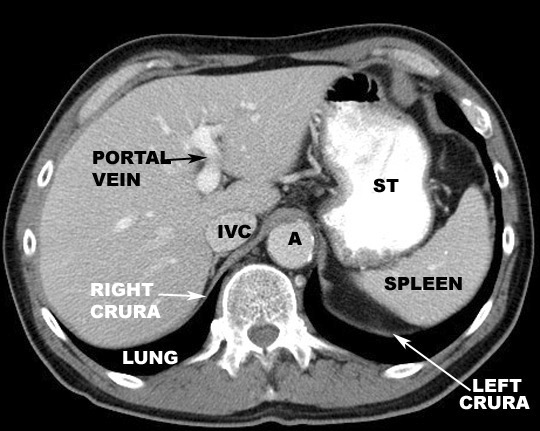

Identify the diaphragm. Click the image for labeling.